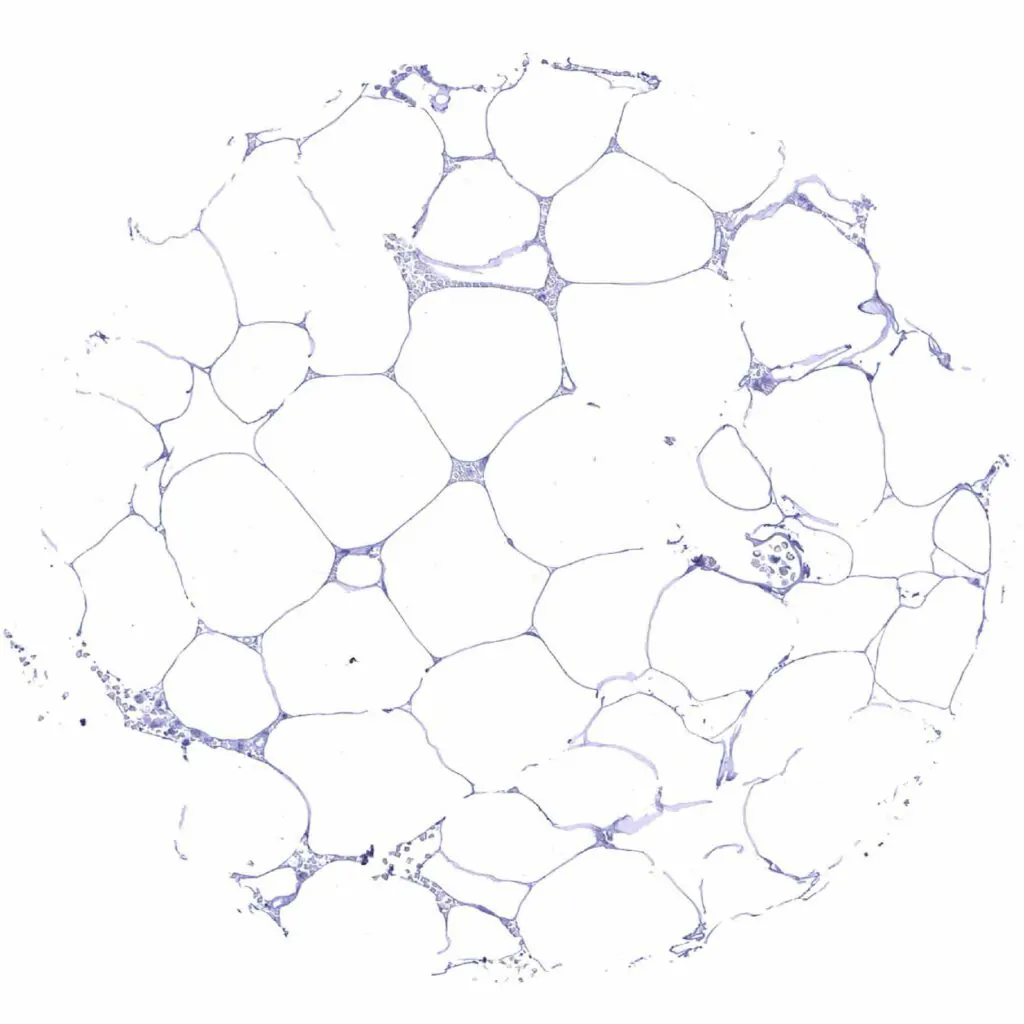

Fat